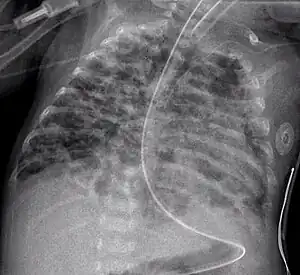

• The air bronchogram sign, where branching radiolucent columns of air corresponding to bronchi is seen, usually indicates air-space (alveolar) disease, as from blood, pus, mucus, cells, protein surrounding the air bronchograms. This is seen in Respiratory distress syndrome[9]